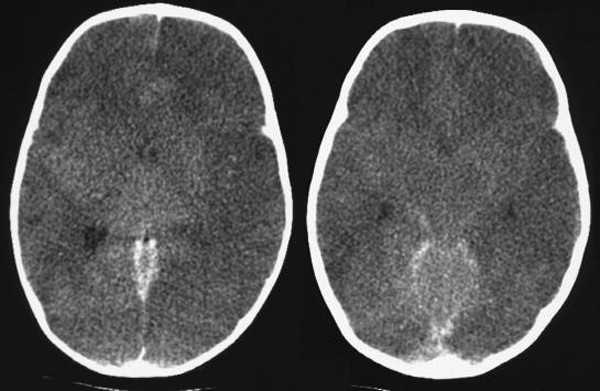

В настоящее время одна из ключевых ролей в диагностике отека мозга принадлежит КТ. Получая послойные снимки головного мозга, данная методика позволяет визуализировать признаки патологии, к которым относят деформацию желудочковой системы мозга, уменьшенное пространство между костной тканью черепа и мозгом, сдавление желудочков. КТ позволяет точно определить область локализации, выраженность, распространенность отека, установить причины патологии, выявить признаки компрессии головного мозга.

Другими признаками патологии являются изменение величины или исчезновение на снимке желудочков и субарахноидальных щелей.

Отметим важную роль КТ в диагностике гидроцефалии, которая также характеризуется патологическим заполнением мозговых тканей жидкостью. Гидроцефалия головного мозга на КТ изображениях выглядит как расширение желудочков мозга. При этом их ширина на коронарных и аксиальных срезах сравнивается с нормой - ширина передних рогов не должна быть более 12-14 мм у пациентов среднего возраста, 15-16 мм у пациентов пожилого возраста. Также существуют специальные желудочковые индексы, на основании которых может быть достоверно диагностирована данная патология. Помимо этого, для понимания характера этого нарушения (окклюзионная либо заместительная) измеряют ширину латеральных ликворных пространств. В первом случае ликворные пространства являются суженными, желудочки резко расширены и имеют вздутый вид, а угол между боковыми желудочками мозга в коронарной проекции является меньшим, чем 110 градусов. При угле более 110 градусов, равномерно расширенном наружном и внутреннем ликворном пространстве можно диагностировать атрофические мозговые нарушения.

Также при помощи КТ можно отслеживать изменения объемов мозга и диагностируемого участка отека, проводить оценку сопутствующих деформаций структур головы и выполнять динамический контроль выраженности отека и изменения величины и формы желудочков мозга.

Другим современным методом диагностики отека мозга является МРТ, с помощью которой точно определяют область отека, размеры и форму мозговых желудочков, цистерн головного мозга, субарахноидального пространства, а также устанавливают причину патологического процесса.